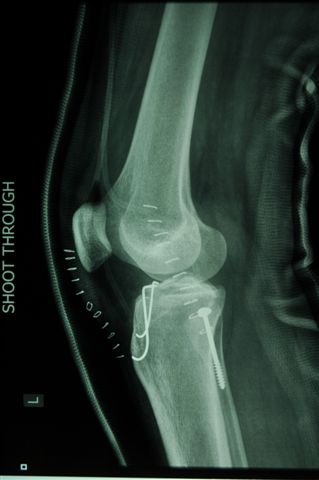

Как вариант фиксации межмыщелкового возвышения предлагаю фиксацию двумя спицами - технически гораздо проще , чем проволочной петлей и вполне стабильно.

В приложении Ргграммы- спицы проводятся ретроградно через фрагмент возвышения, загибаются, подтягиваются  и загибаются со стороны внутреннего мыщелка.